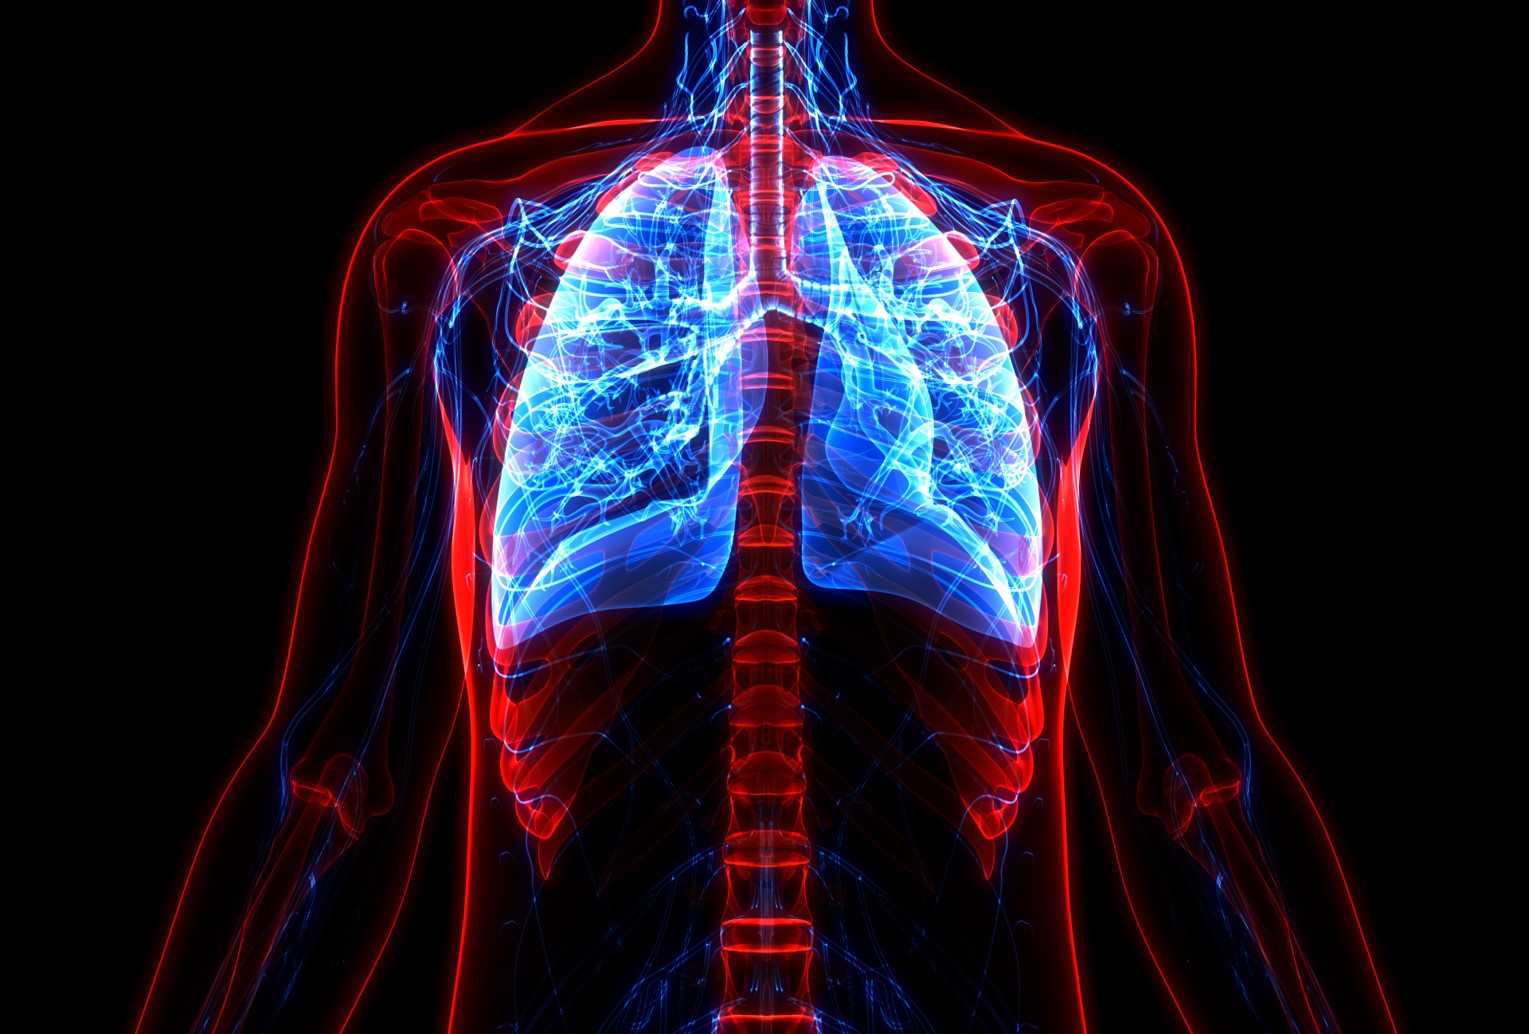

新型コロナ禍で多くの方が、呼吸の重要性、免疫力の重要性、自律神経の重要性、酸素の大切さに気が付いてきました。

肺活は造語ですが、私どもは以下のように定義しています。

肺活は、呼吸に関係する機能を向上させるだけにとどまらず自律神経機能も向上させ、生体

のソフトウエア、ハードウエア全体の機能を向上させる次世代の健康法・トレーニング法で、

- 呼吸筋強化、呼気筋、吸気筋筋力強化と持久力強化

- 呼吸法による自律神経機能向上

- 胸郭可動域拡大ストレッチによる呼吸機能の向上(酸素摂取能力向上)

を総称します。

肺活を行うメリットは、呼吸機能が向上するだけではなく、呼吸法による自律神経機能向上を目的としています。

生命維持において、酸素と栄養は不可欠です。 栄養に関してはある一定期間供給されなくても生命維持のために代替の方法を用いて対応 可能ですが、酸素は取り込むための呼吸機能がなければ、維持することはできません。 呼吸機能を司る肺は、人体において最も重要な臓器の一つです。

肺は加齢に伴い、機能が低下して、20 代をピークに衰えはじめ、喫煙者では40 代に急激な 機能低下を引き起こします。 肺機能が低下すると、咳や痰、軽い動作での息切れなど、日常動作でも症状として現れます。 酸素を十分に取り込むためには「肺胞」の働きが重要ですが、一度肺胞が破壊されてしまうと再生することはありません。

よって、残存する呼吸機能を維持・向上することが肺活の呼吸トレーニングの目的における 重要なポイントとなります。

私どもが提案する 肺活の中での呼吸トレーニングとしまして、呼吸関連筋肉群をダイナ ミックストレッチすることで、胸郭可動域拡大を目的としています。 専門機器を必要とせず、手軽にどんな場でも短時間で実施可能です。 本トレーニングで強化される筋肉は、呼吸の主たる筋群、横隔膜、外肋間筋、内肋間筋をは じめ、胸鎖乳突筋、斜角筋、僧帽筋、小胸筋、前鋸筋、外腹斜筋、腹横筋、腹直筋、内腹斜 筋、菱形筋、脊柱起立筋です。 横隔膜の動きで、胸郭内圧が変化し肺が拡張、収縮します。 外肋間筋は肋骨を上方へ引き上げ吸息時に働き内肋間筋は肋骨を下方へ引き下げ呼気時に 働きます。 その他の筋肉は、状況に応じて呼吸をサポートします。胸鎖乳突筋、後斜角筋は、運動など息が上がる状態で胸郭を挙上する役割を果たします。 筋肉は加齢とともに衰えてしまい、特に呼吸器系は加齢の影響が顕著で呼吸器疾患の悪化 は気付きにくく、進行してしまった状態で発見されることが多いのです。

○肺活で強化される筋肉

- 横隔膜

- 外肋間筋

- 内肋間筋

- 胸鎖乳突筋

- 斜角筋

- 僧帽筋

- 小胸筋

- 前鋸筋

- 外腹斜筋

- 腹横筋

- 腹直筋

- 内腹斜筋

- 菱形筋

- 脊柱起立筋

○呼吸筋の働き

- 横隔膜

胸郭内圧が変化し肺が拡張、収縮させます。 - 外肋間筋

肋骨を上方へ引き上げ吸息時に働きます。 - 内肋間筋

肋骨を下方へ引き下げ呼気時に働きます。 - 胸鎖乳突筋、後斜角筋

運動など息が上がる状態で胸郭を挙上する役割を果たします。 - その他の筋肉

状況に応じて呼吸をサポートします。